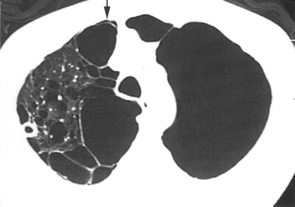

また、巨大ブラの気胸の場合は診断がCTで困難な事があります。その読影所見のポイントとしては圧排もしくは固まった肺がある、非解剖学的な透過性亢進がある、2重壁サインがある、というものです4。2重壁サインとは胸壁とブラの2重の壁がCTで認められるというものです。これはブラの壁の内外両側に空気のアウトラインが見える事をいい、これを認める場合には気胸の診断となります(下図矢印が2重壁サイン)。

図はGayle M. Waitches et al; Usefulness of the Double-Wall Sign in Detecting Pneumothorax in Patients with Giant Bullous Emphysema Am J Roent 2000; 174 : 1765-1768より